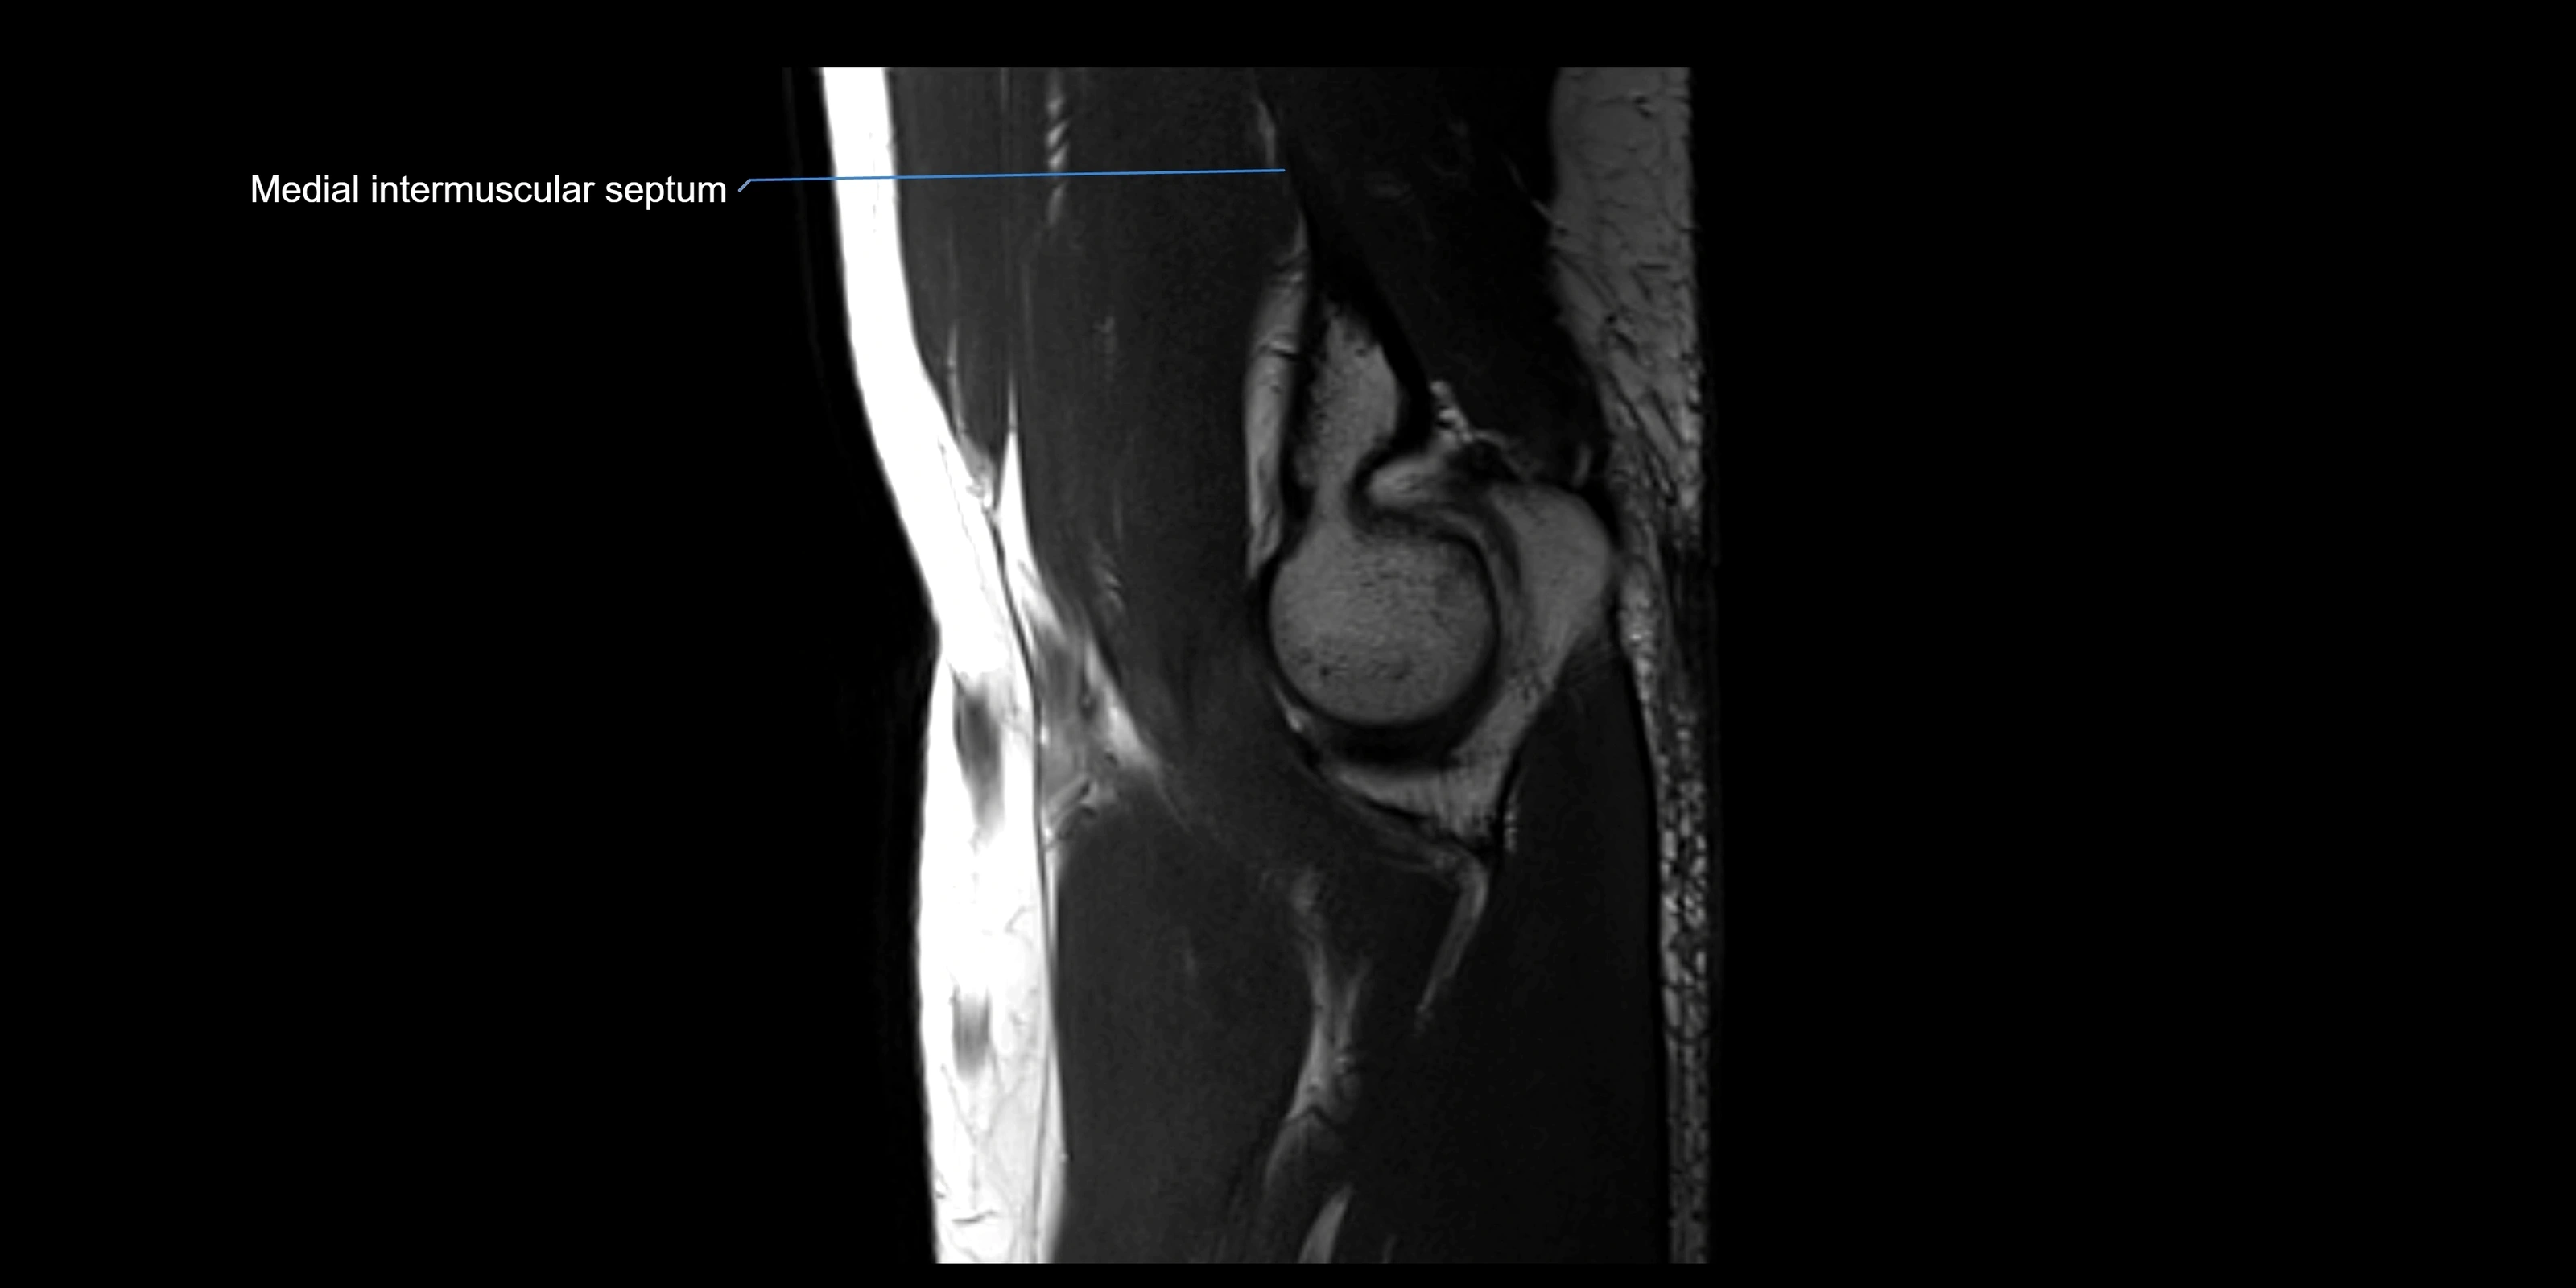

MRI images

image